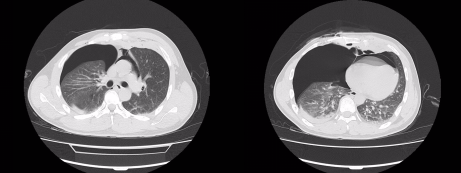

急诊医生对胸部伤口进行紧急加压包扎,随后经CT检查发现李师傅出现了心包积气与气胸,情况十分危险,随即联络胸外科王保毅主任进行紧急手术。

入院CT显示患有心包积气与气胸

术前术后心包积气情况对比